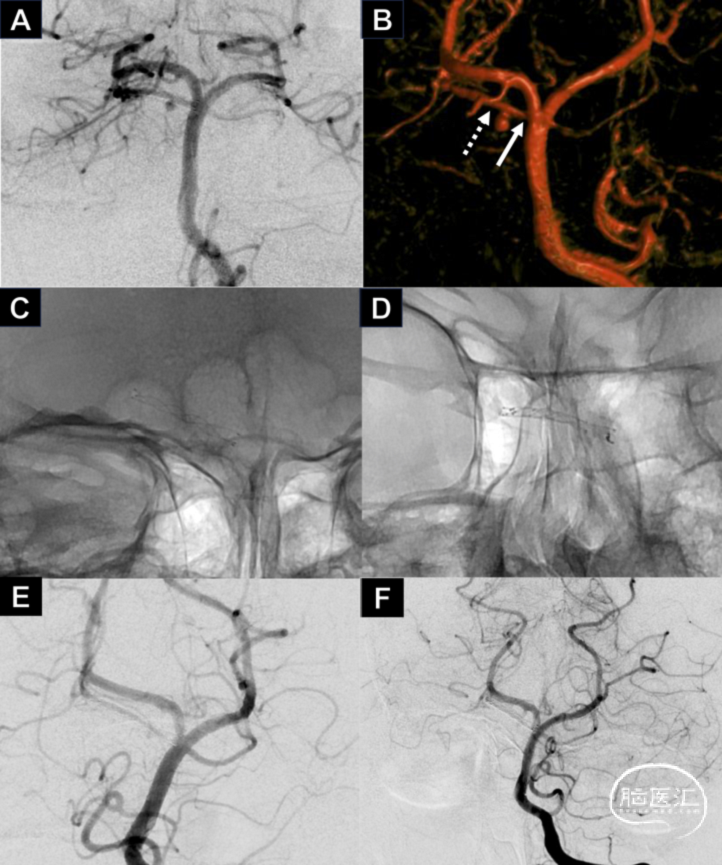

图2.右侧SAC远端假性动脉瘤,二期使用FRED Jr治疗 (详见病例介绍)。

本文介绍了使用LVIS Jr及FRED Jr分期治疗右侧SAC远端破裂假性动脉瘤的病例,分期治疗避免了出血痉挛期载瘤动脉的闭塞,LVIS Jr植入后动脉瘤能够稳定但未愈合。二期非急性期植入FRED Jr最终治愈了该动脉瘤。本病例提示,后循环小血管破裂假性动脉瘤可以在急性期使用LVIS Jr稳定动脉瘤,二期再使用FRED Jr行治愈性栓塞。